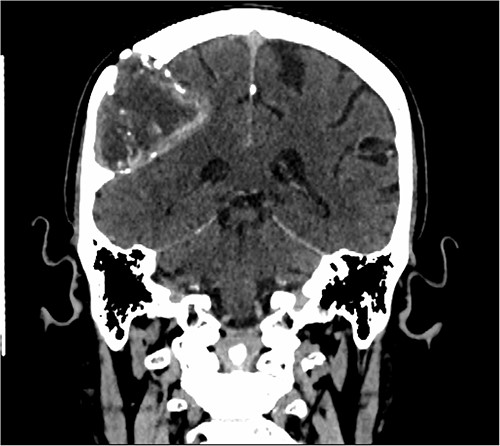

Our patient is a 76-year-old gentleman with medical history of hypertension and lumbar spondylosis. He did not have any previous history of trauma or systemic infections. He had presented to his local hospital with a 2-day history of left arm numbness. He did not report any headaches or giddiness. On clinical assessment, he did not have any neurological deficits. A CT brain and MRI brain (Figs 1–5) with contrast revealed a 53 × 53 × 41 mm partially calcified, heterogeneously enhancing conical shaped right extra-axial parietal convexity lesion. The overlying calvarial bone was remodelled and possibly eroded. There was evidence of prior haemorrhage within the lesion and scattered internal and peripheral calcification. Based on these characteristics, the possible diagnoses were that of an intraosseous meningioma, haemangioma and giant cell tumour. Patient was consented for craniotomy and excision of the tumour.

T2-weighted axial MRI scan showing the lesion with intralesional haemorrhagic products. There is no evidence of dural invasion.

T1-weighted contrast-enhanced coronal MRI scan showing the lesion with intralesional haemorrhagic products. There is no evidence of dural invasion.